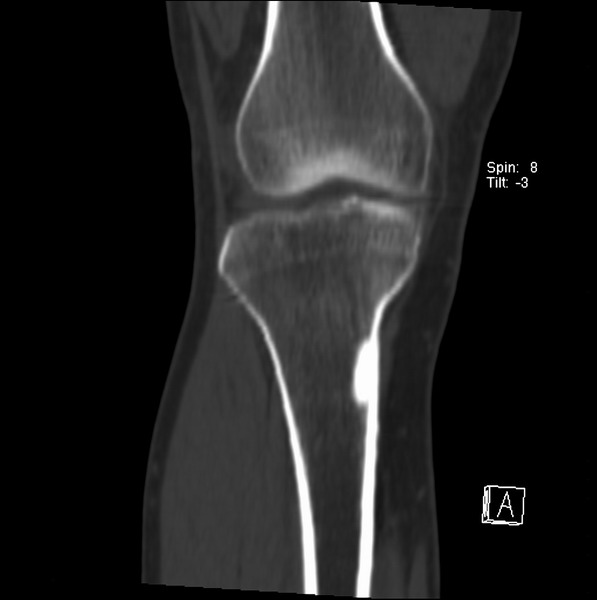

右侧膝关节疼痛一月

男、48

股骨下段、胫骨上段。

1、股骨干骺端病变考虑干骺端纤维性皮质缺损愈后(非骨化性纤维瘤)改变,胫骨近端内生骨瘤(或干骺端纤维性皮质缺损愈后改变);

2、骨关节炎,骨质增生,股骨外侧髁退变性囊肿(关节面软骨下囊肿);

1、股骨干骺端病变考虑干骺端纤维性皮质缺损愈后(非骨化性纤维瘤)改变,胫骨近端内生骨瘤;

股骨干骺端病变考虑非骨化性纤维瘤。